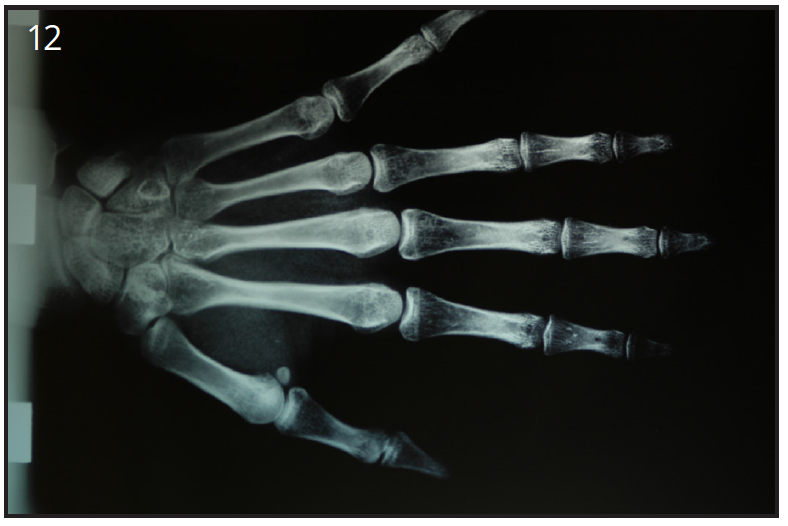

Young patient under 16-17 years old cannot receive dental implants. A hand-wrist radiograph is taken to determine if growth is complete . (Figure 12) If the patient is still growing, a resin-bonded bridge can be used as an option until their growth is complete and they are an implant candidate.

Figure 12 – Hand-wrist radiograph verifies complete growth

Figure 12